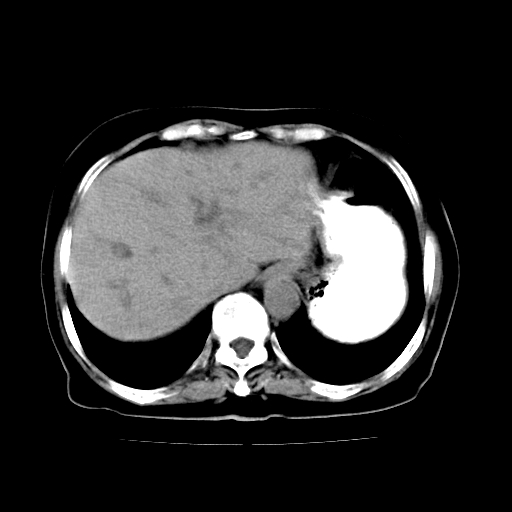

女,74岁,上腹部不适、腹胀两月余,黄染四天。请大家看看肿块周围血管情况。

肝内外胆管增粗,梗阻点位于胰头部,胰头增大,轻度不均性强化(较正常胰腺强化低,胰体尾呈退化';羽毛状';),孝虑为胰头ca.

肝内外胆管和胰管扩张,胆囊明显增大,胰头外形增大,无强化,考虑:胰头癌伴肝内外胆管、胆囊扩张积液。

肝内外胆管增粗,梗阻点位于胰头部,胰头增大不均性明显强化,胰体尾部萎缩,胰管显影,虑为胰头ca.

肝内外胆管及胆囊扩张,胰管扩张,但“双管征”不明显,胆总管下段内见软组织有强化影,肠系膜上静脉推移不是很明显,考虑胆总管下段癌可能大。